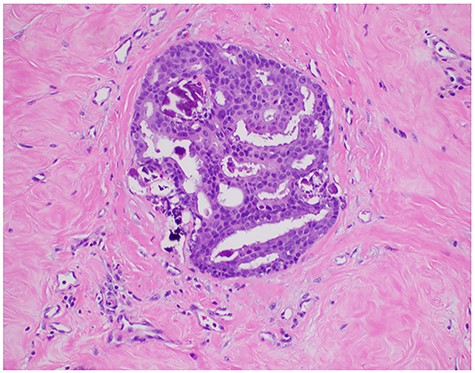

Stereotactic core needle biopsies of both breasts were performed the following week confirming the presence of bilateral intermediate grade ductal carcinoma in situ (DCIS). Subsequent immunohistochemistry staining found both left and right breast cancers to be strongly positive for both estrogen receptor (ER) and progesterone receptor (PR) presence with positive nuclear expression in cell fractions of 90:60% (ER:PR) on the left and 100:100% (ER:PR) on the right. Upon subsequent disclosure of his diagnosis and discussion of recommended treatment options, the patient elected to proceed with a bilateral mastectomy with sentinel lymph node biopsy.

The patient underwent surgery <1 month after initial diagnosis. The surgery proceeded as planned without complications and was well tolerated by the patient. Perioperative management followed the institution-wide opioid-sparing enhanced recovery after (breast) surgery protocol, affording our patient a safe discharge home on postoperative Day 1. Final surgical pathology confirmed bilateral presence of intermediate grade (non-comedo) DCIS with (at least) 3-mm clear margins and negative node involvement (Figs 3, 4), yielding a favorable diagnosis of Tis N0 M0 (Stage 0) disease.

Pathologic microscopy of right breast ductal carcinoma in situ with magnified images highlighting absence of local invasion.